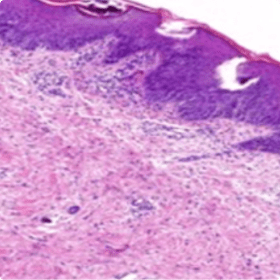

Dans les cas de psoriasis plus atypiques, une biopsie de la peau pourrait être utile10

un infiltrat neutrophilique dominant.

Infiltrat neutrophilique dominant